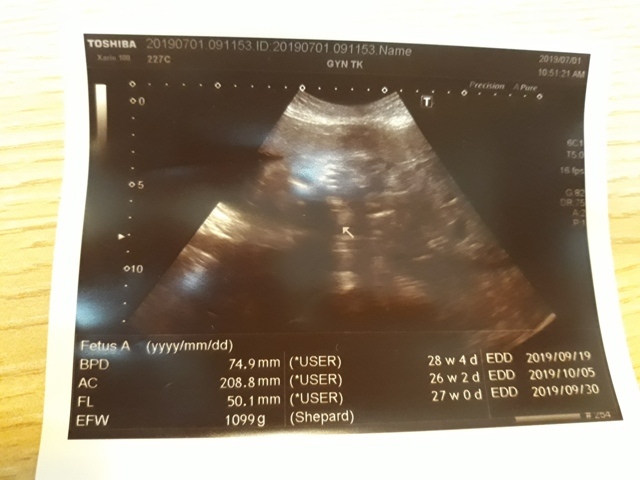

妊娠糖尿病數值為124,超過140就是超標,小純的妊娠糖尿病檢驗結果為正常的數值。接著,去照超音波,自從05月22日和06月03日的產檢,發現小飛的FL(腿長)比實際天數少一個星期後,讓小純感到很鬱悶,他最近很努力的吃鈣片,希望能讓小飛的腿長趕上進 度,今天一量,27週又0天,雖然還是落後實際的天數(27週又3天),但已漸漸趕上了。

27週又3天↓

近六次產檢資料統計

| 日期/項目 | BPD | AC | FL | EFW | 心跳 |

| 2019年03月04日 | 無資料 | 無資料 | 無資料 | 無資料 | 無資料 |

| 2019年04月01日 | 28.9mm | 77.9mm | 14.2mm | 107g | 153 |

| 2019年04月29日 | 41.7mm(44%) | 125.7mm(61%) | 28.9mm(103%) | 241g(125%) | 150 |

| 2019年05月22日 | 53.4mm(28%) | 160.6mm(28%) | 34.6mm(20%) | 408g(69%) | 150 |

| 2019年06月03日 | 58.3mm(9%) | 179.6mm(12%) | 38.2mm(10%) | 584g(43%) | 157 |

| 2019年07月01日 | 74.9mm(28%) | 208.8mm(16%) | 50.1mm(31%) | 1099g(88%) | 141 |

| BPD:胎兒頭骨橫徑 AC:胎兒腹圍的長度 FL:胎兒大腿骨的長度 EFW:胎兒的體重 括弧內百分比為較上次產檢的成長比例 | |||||